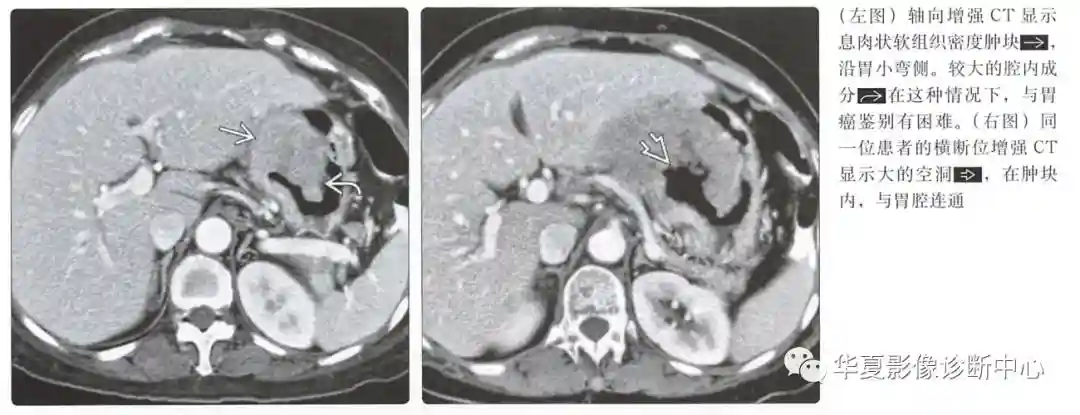

动脉期图像呈低或高血供,边界清楚的黏膜下肿块;溃疡和坏死是常见的

具有大的腔内成分的肿瘤可能类似原发性胃癌

邻近胃壁的局灶性增厚和胃出口阻塞可以帮助区分GIST

GIST很少是环周性的